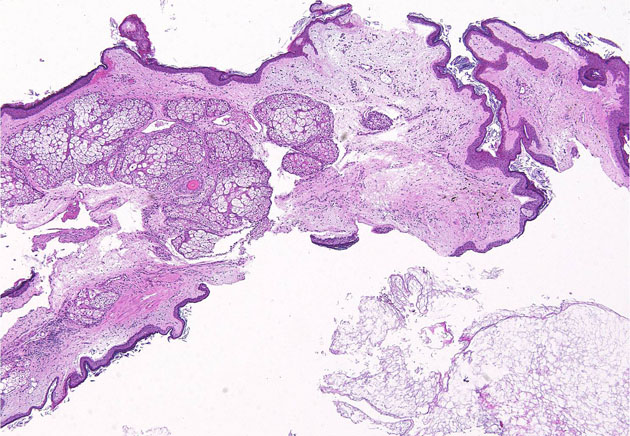

病理所見

豊富な皮脂腺 sebaceous gland を有する扁平上皮 epidermis とケラチン dry keratin material(右下)が特徴です

皮脂腺を有する扁平上皮とkeratin material (右下)の概観